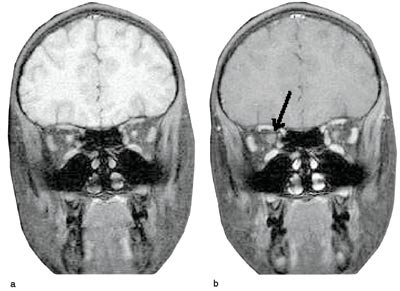

Ved kontroll etter avsluttet behandling (seks uker etter utskrivning) fant man nærmest normalisering av tilstanden også på høyre øye. Visus var nå 0,8+ på høyre og 1,0 på venstre øye, og begge papiller hadde normalt utseende. Det ble gjort en ny MR-undersøkelse av hodet, denne gangen med kontrast, og den viste svak kontrastoppladning i periferien av høyre optikusnerve, som kan tyde på at det fremdeles var lett betennelse i synsnerven (fig 1).

Differensialdiagnostisk er det viktig å undersøke i forhold til forhøyet intrakranialt trykk, encefalitt/meningoencefalitt og sjeldne tilstander som for eksempel vaskulitt. I den sammenheng kommer CT/MR av hodet, spinalvæskeundersøkelse og blodprøver naturlig inn. Ved optikusnevritt kan MR en sjelden gang påvise bilateral fortykkelse av synsnerven. Dette er et typisk funn ved optikusnevritt (11, 12).